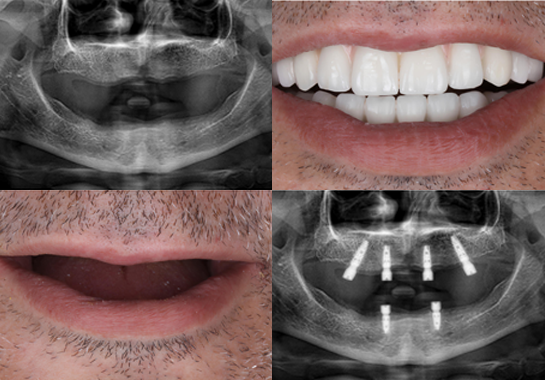

La greffe osseuse dentaire est une procédure qui permet de restaurer le volume osseux de la mâchoire, souvent indispensable avant la pose d’implants dentaires. Cette technique est nécessaire pour de nombreux patients envisageant des implants, car elle offre une solution à un problème fréquent en implantologie : le manque de volume osseux. La perte osseuse peut survenir pour diverses raisons, notamment suite à une extraction dentaire, une maladie parodontale avancée ou un traumatisme facial.

Tout commence par une consultation approfondie et une planification détaillée. Le chirurgien-dentiste réalise un examen clinique minutieux, complété par des examens radiologiques avancés comme la tomodensitométrie 3D. Ces informations permettent de choisir le type de greffe le plus approprié et de planifier précisément l’intervention.

Enfin, le suivi et la cicatrision s’étendent sur plusieurs mois. Des rendez-vous de contrôle réguliers permettent au chirurgien de surveiller la progression de la cicatrisation. La durée moyenne de cicatrisation avant la pose d’implants varie généralement de 4 à 6 mois, selon le type de greffe et la réponse individuelle du patient.

La greffe osseuse dentaire permet la pose d’implants dans des cas qui auraient été auparavant impossibles, offrant ainsi une solution à des patients qui n’avaient pas d’autres options. De plus, elle améliore considérablement l’esthétique du sourire en restaurant les contours naturels de la mâchoire. Sur le long terme, la greffe osseuse augmente la longévité des implants dentaires en leur fournissant une base solide. Elle contribue également à prévenir d’autres problèmes bucco-dentaires liés à la perte osseuse, comme l’affaissement des tissus mous du visage.

L’intervention chirurgicale est réalisée à Istanbul, dans des installations ultramodernes. Les praticiens d’Esteworld sont reconnus pour leur expertise en implantologie et en chirurgie maxillo-faciale. Cette étape permet de bénéficier de soins de haute qualité à des coûts plus avantageux qu’en France.